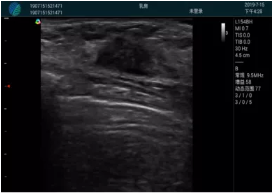

清晰顯示腺體內(nèi)低回聲快影,邊界清晰,包膜較光滑

確定進(jìn)針路徑并實(shí)時(shí)監(jiān)測抽吸針與腫塊位置關(guān)系

抽吸針進(jìn)入腫塊內(nèi)部進(jìn)行旋切

抽吸過程中可見腫塊明顯縮小,并根據(jù)腫塊位置改變針道位置